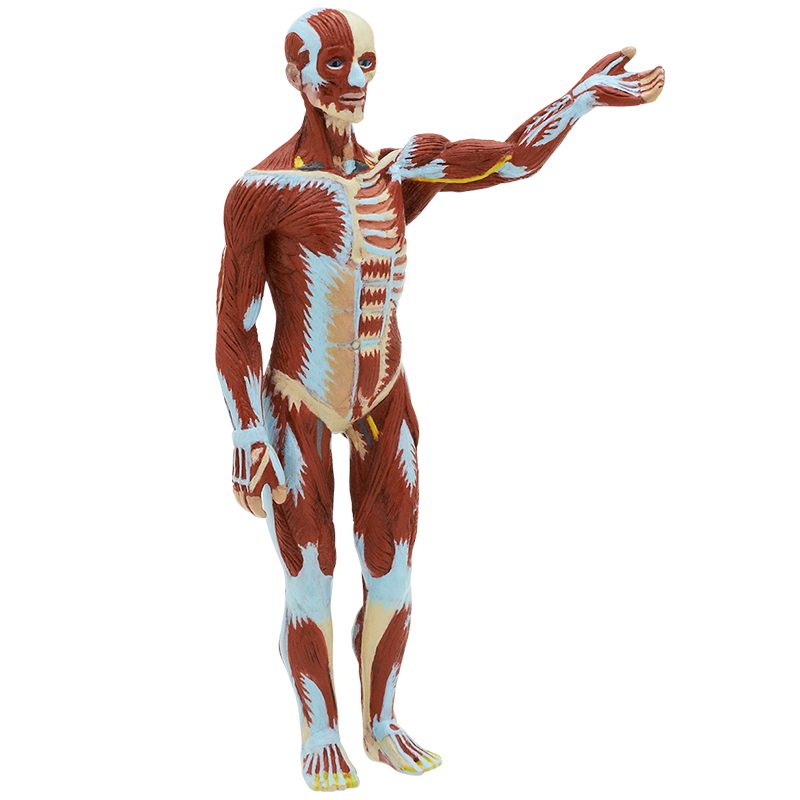

大人 可愛い 服 全身骨格(神経筋肉系)模型 引き取りのみ その他